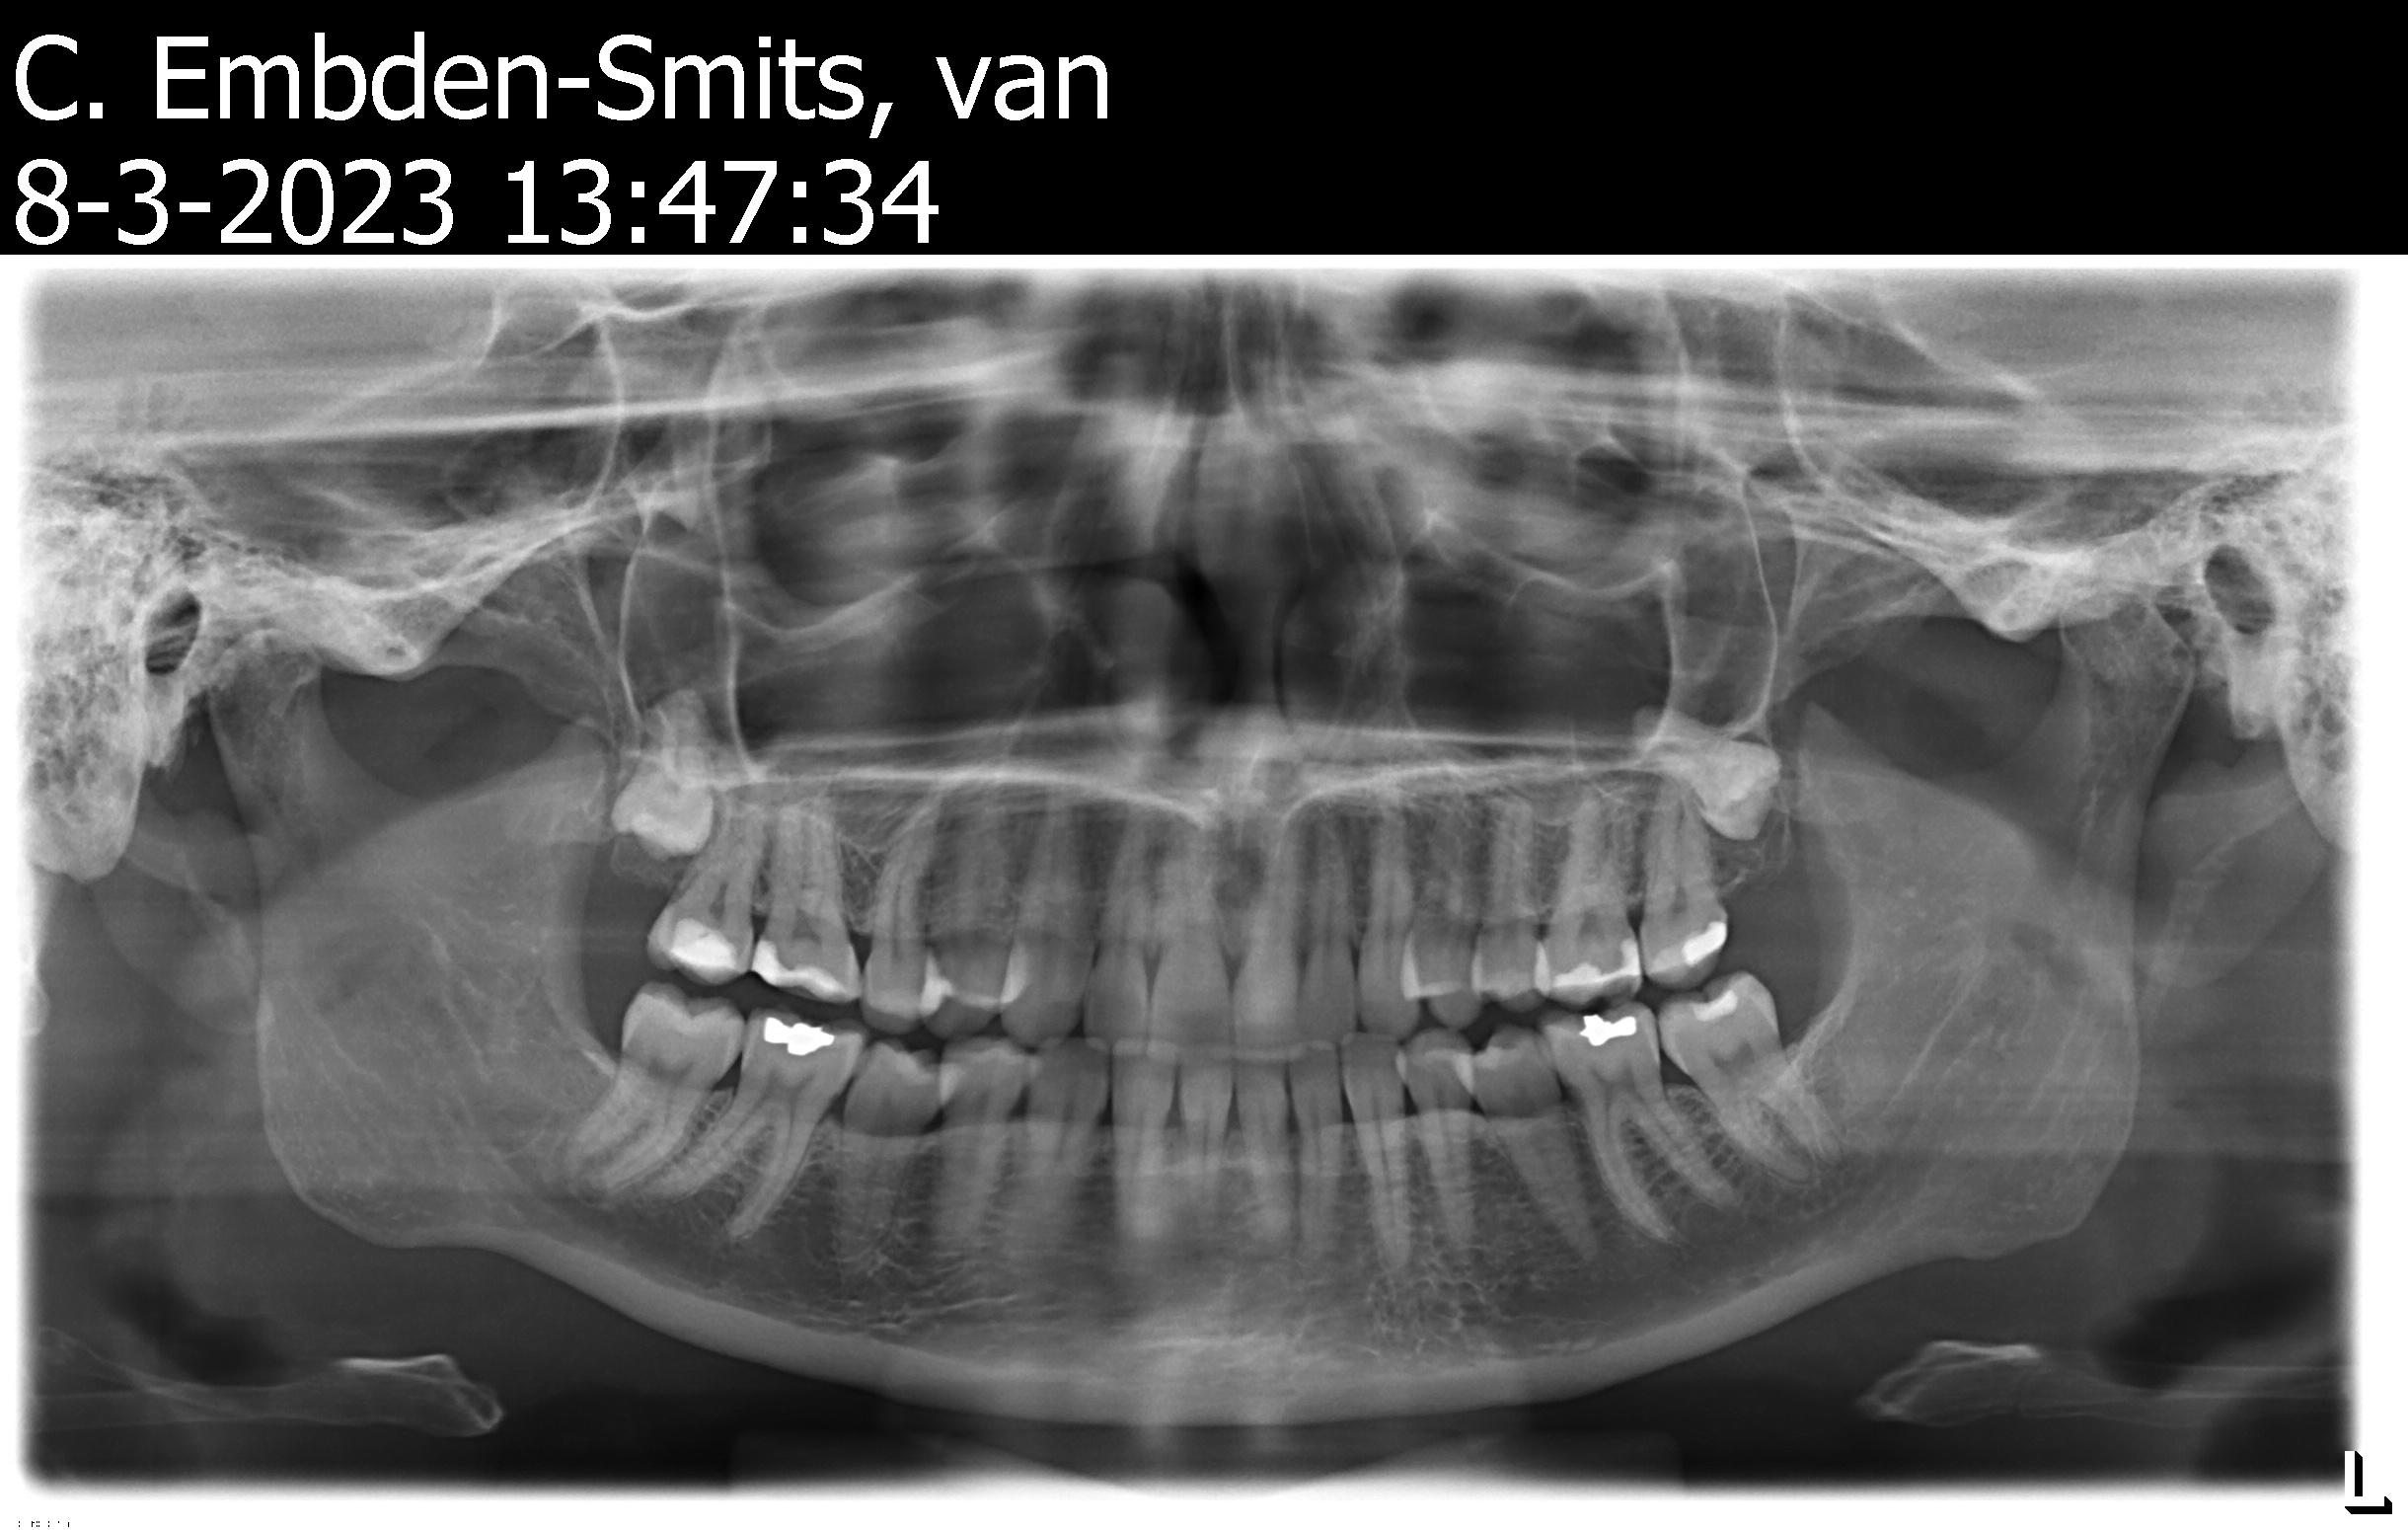

Afgelopen woensdag naar een andere tandarts gegaan, want eigen was met vakantie, omdat ik toch nog steeds last had. Weer foto gemaakt en er was op de laatste kies toch nog iets niet goed. Die heeft mij, dit keer met verdoving, opnieuw gevuld en daar bleek gewoon tandbederf onder te zitten. Ook was er op de foto een verstandskies te zien maar die zit nog in het kaakbot. Kan wel wat druk geven gaf ze aan. Eigenlijk ging het daarna beter tot zaterdagmiddag. Ineens toch weer last van de eerste kies die gevuld was, was ook een grote vulling. Ik ga nu morgen naar een andere tandarts voor een second opinion. Heb vannacht weer niet kunnen slapen en loop ondertussen op paracetamol en ibu. En ik heb normaal nooooooit wat met mijn gebit. Ga netjes naar de tandarts 1 keer per half jaar. Maar sinds vorig jaar bij deze tandarts omdat de vorige overleden was. Ik voel mij zo niet serieus genomen, werd weggestuurd met de boodschap niet zeuren en kijk het aan en vervolgens bleek er wel degelijk tandbederf onder een vulling te zitten. Ik ben dus bang dat de eerste kies, waar ik nu last van heb, ook niet goed gevuld is en dat dit de pijn veroorzaakt. Een drukkende pijn, niet kloppend. Gisteren ook een vieze smaak in mijn mond, dat is nu weer beter.

De verstandskies zit ook te drukken en zorgt naar mijn gevoel ook voor pijn, die hangt nu ter hoogte van de wortels van de laatste kies. Morgen ga ik naar de nieuwe tandarts om te horen hoe of wat. De verstandskies moet er waarschijnlijk sowieso uit, daar heb ik nu een afspraak voor bij de kaakchirurg aanstaande woensdag al. Dat is heel snel, dacht daar zit weken wachttijd op.

Ik moet overigens morgen naar de KC omdat er nog geen goede diagnose gesteld kan worden. De verstandskies drukt en de kies die gevuld is kan daar last van hebben. Het kan ook zo zijn dat de pijn uit de gevulde kies komt omdat de vulling vrij diep zit en tegen het zenuwuiteinde lijkt te duwen. Maar dat kon dus ook komen door druk vanuit de verstandskies. Kortom, morgen hopelijk opheldering en een concrete diagnose.

Chan79

Mag ik u nog 1 vraag stellen? Zou u een blik kunnen werpen op de overzichtsfoto van de kaakchirurg die begint maart is gemaakt? Ik zou graag uw bevindingen willen van de verstandskies die daar ook nog “hangt “ en of die ook onderdeel kan zijn van het klachtenpatroon.